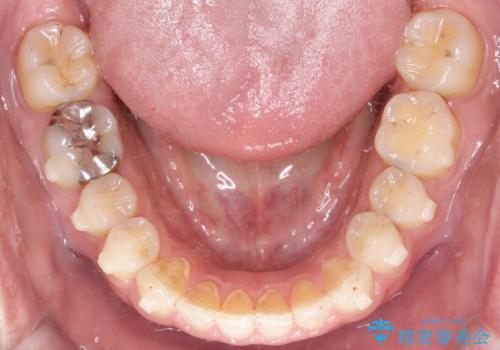

【インビザライン】前歯の隙間を閉じたい

- 前歯の隙間を主訴に来院されました。

マウスピース矯正にて、隙間を綺麗に閉じることができ満足していただきました。

前歯の隙間を閉じる際は、前歯部の突き上げが懸念されるため、適切な治療計画が必要となります。